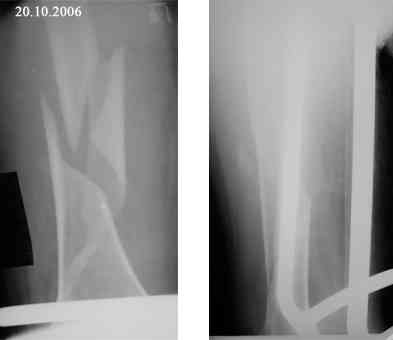

Re: Оскольчатый перелом бедра. Помогите определиться с дальнейшей тактикой

Представляю вашему вниманию снимки в динамике